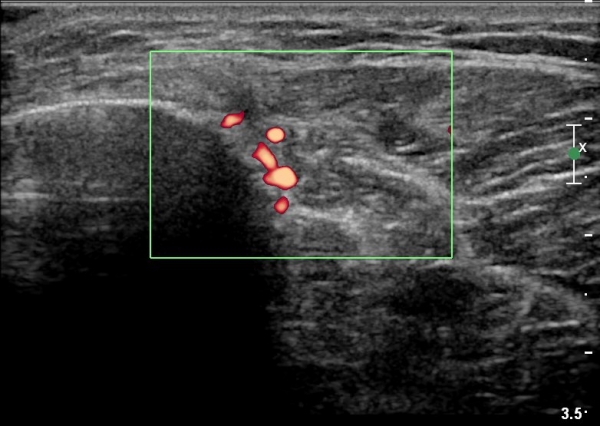

[¹«¸­] °æ°ñ ÇǷΰñÀý ÃÊÀ½ÆÄ¼Ò°ß(sonographic findings of stress fracture of tibia)

¿ìÃø ¹ß¸ñ°ú ¾Æ·§´Ù¸® ÅëÁõ(±â°£ 2ÁÖ)

±º´ë¿¡ ÀÔ´ëÇÏ¿© ÈÆ·ÃÀ» ¹ÞÀº º´·ÂÀÌ Àִ ȯÀÚ´Â ¾à 2ÁÖ ÀüºÎÅÍ ¹ß¸ñ ºÎÀ§ÀÇ ÅëÁõÀÌ ÀÖ´ø Áß

ÃÖ±Ù¿¡´Â ¹ß¸ñ À§ ¾Æ·§´Ù¸®¿¡ ÅëÁõÀÌ ¹ß»ýÇÏ°í ½ÉÇÏ°Ô °ÉÀ¸¸é ½ÉÇØÁö´Â ¾ç»óÀÓ

¾Æ·§´Ù¸® Áß°£ ºÎÀ§¿¡ °æ¹ÌÇÑ ¿¬ºÎÁ¶Á÷ ºÎÁ¾ÀÌ °üÂûµÇ°í ¾à°£ÀÇ ±¹¼ÒÀû ¾ÐÅëÀ» º¸ÀÓ.

ÃÊÀ½ÆÄ °Ë»ç

¹Ì¼¼ÇÏ°Ô ¿¬ºÎÁ¶Á÷ ºÎÁ¾°ú °¡°ñ Çü¼ºÀÌ °üÂûµÊ.